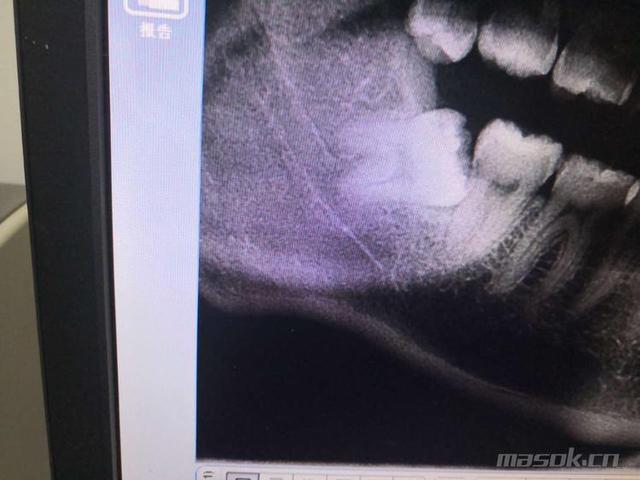

下面这个就没有这么可爱了:

不仅两个牙根是分开的,而且距离下颌神经管很近,这样拔牙难度就增加了许多。医生需要把智齿分成几小块,再一个一个薅出来。

如果牙根不幸折断(通常小于2 mm),又紧邻神经管,为了保护神经,医生有可能就会不再力求全部拿出来,剩余的一点点就会留在骨头里。